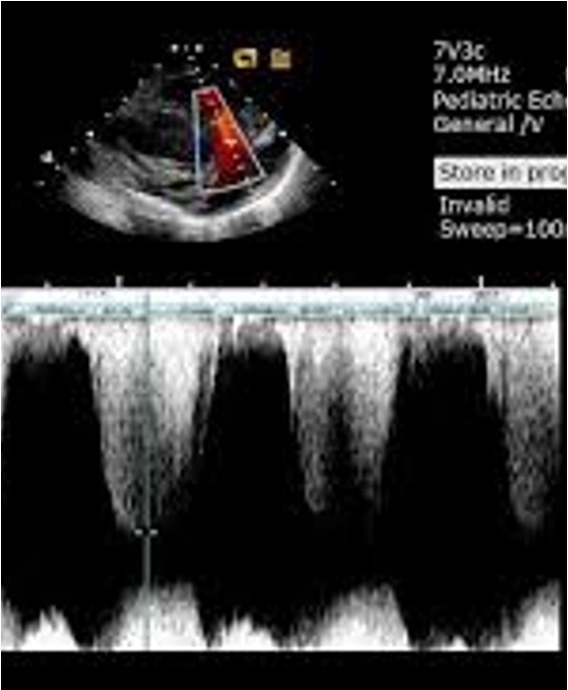

16

Q

For a PSAX RVOT PW image we need to look for a PV “closing click” what should these look like?

A

These are the really thing lines under the baseline

What should the SV measure on the RV side of the PV?

For PSAX RVOT PW what should we measure?

Peak velocity or trace VTI